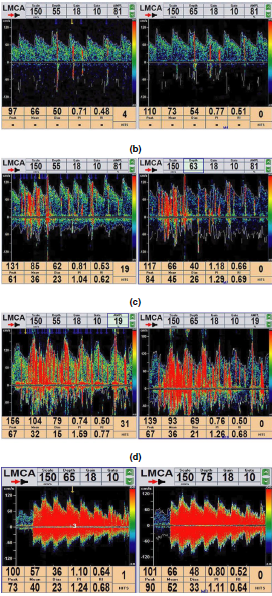

Results: Overall, 113 migraine with aura (MA) and 192 migraine without aura (MO) patients were included. Patients with MA and RLS (MARLS+) had a higher frequency for sensory aura symptoms than those with MA without RLS (MARLS?) (27.4% vs.10.0%, p = .03). Patients with MO and RLS (MORLS+) presented with significantly

younger initial age of migraine onset and experienced more severe pain intensity than those with MO without RLS (MORLS?) (mean ± SD, 25.6 ± 8.9 vs. 29.8 ± 12.7 years,p = .008 and 5.9 ± 1.4 vs. 5.3 ± 1.3, p = .006, respectively). There was no relationship between the degree of shunt and the clinical parameters of headache.

Conclusions: Our results indicate that MO patients presented with a younger initial age of migraine onset and that sensory aura symptoms in MA patients may predict the presence of RLS. However, we did not find support for relationship between the

degree of shunt and clinical parameters of headache.